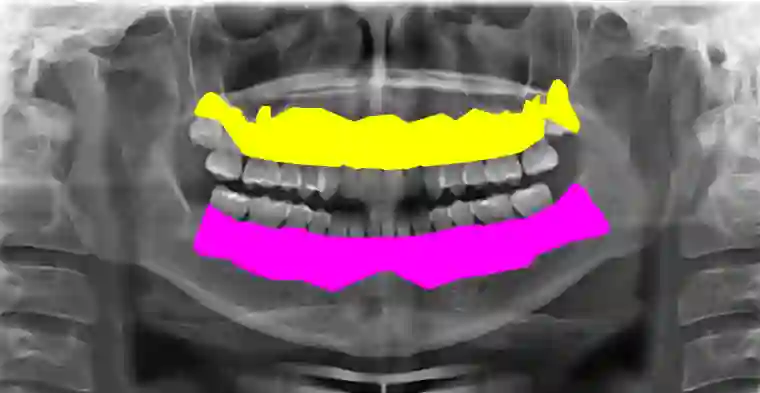

Accurate understanding of anatomical structures is essential for reliably staging certain dental diseases. A way of introducing this within semantic segmentation models is by utilising hierarchy-aware methodologies. However, existing hierarchy-aware segmentation methods largely encode anatomical structure through the loss functions, providing weak and indirect supervision. We introduce a general framework that embeds an explicit anatomical hierarchy into semantic segmentation by coupling a recurrent, level-wise prediction scheme with restrictive output heads and top-down feature conditioning. At each depth of the class tree, the backbone is re-run on the original image concatenated with logits from the previous level. Child class features are conditioned using Feature-wise Linear Modulation of their parent class probabilities, to modulate child feature spaces for fine grained detection. A probabilistic composition rule enforces consistency between parent and descendant classes. Hierarchical loss combines per-level class weighted Dice and cross entropy loss and a consistency term loss, ensuring parent predictions are the sum of their children. We validate our approach on our proposed dataset, TL-pano, containing 194 panoramic radiographs with dense instance and semantic segmentation annotations, of tooth layers and alveolar bone. Utilising UNet and HRNet as donor models across a 5-fold cross validation scheme, the hierarchical variants consistently increase IoU, Dice, and recall, particularly for fine-grained anatomies, and produce more anatomically coherent masks. However, hierarchical variants also demonstrated increased recall over precision, implying increased false positives. The results demonstrate that explicit hierarchical structuring improves both performance and clinical plausibility, especially in low data dental imaging regimes.